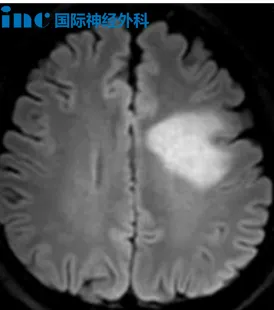

然而,就在半年后,MRI检查显示了位于左侧放射冠、半卵圆中心、胼胝体区的多发占位性病变,且肿瘤性病变的可能性较大。医生的一句话更有如晴天霹雳般砸向他:由于病灶位置深在,术后偏瘫失语的可能性极大。